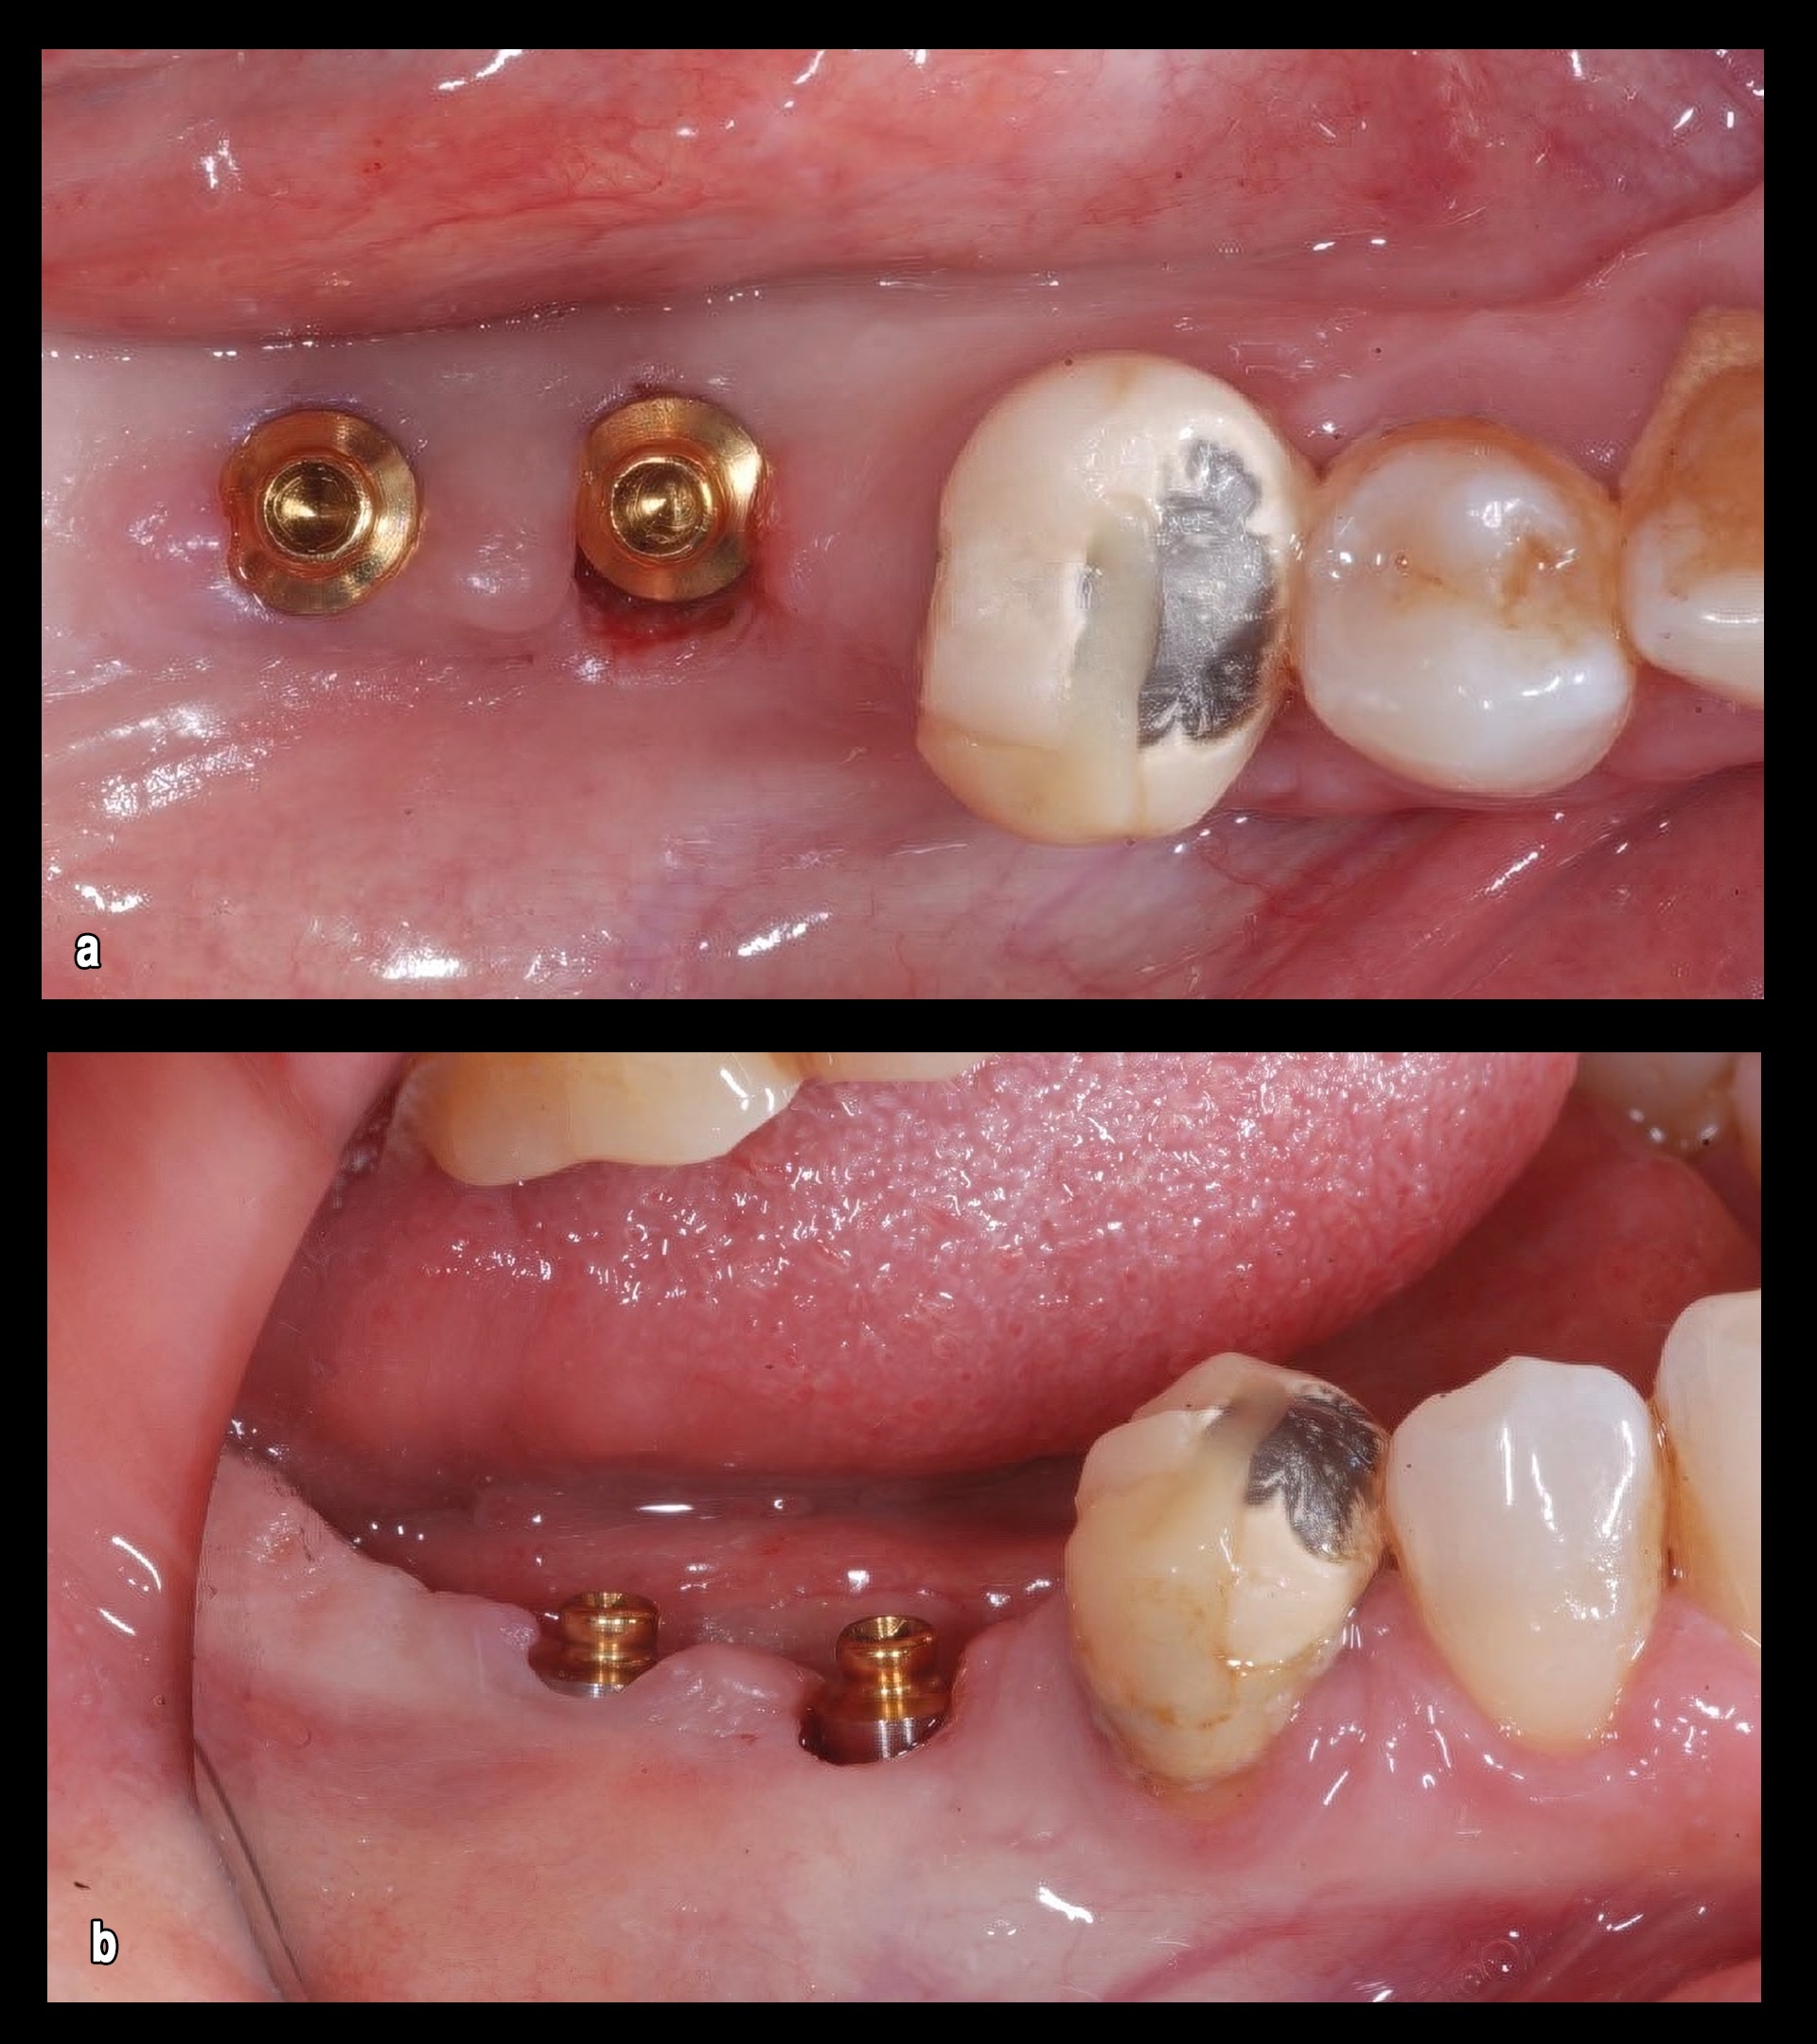

Figura 1. El examen intraoral mostró que los túneles gingivales estaban completamente cerrados (a) para la regeneración del tejido (b), confirmando el tiempo transcurrido desde que se desatornillaron.